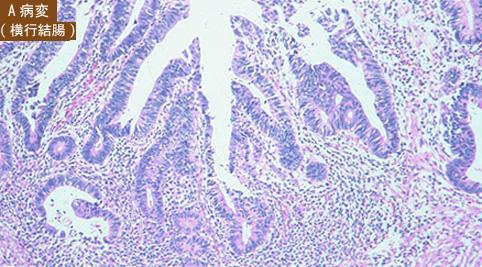

Criteria of Hist.ClassificationMalignant epithelial tumor/Adenocarcinoma

LocationLarge intestine(Colon)/Transverse colon

Macroscopic TypesType 0/IIa (IIa+IIc) Superficial elevated and depressed type

Size15 - 19

Depth of Tumor Invasionsubmucosa